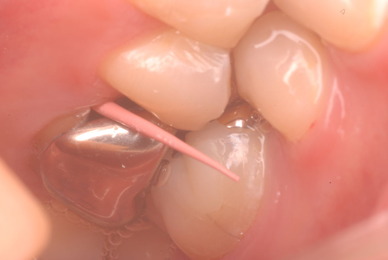

ご自分でやられても歯茎から血が出ないと話をされていましたが、私がブラシを当てると悲惨な状態であることがわかりました。

何故歯が悪くなるのか、歯周病で抜けるのか分からなければ何を入れても歯は悪くなり抜けていくのです。

病気を治しましょう。それから差し歯や入れ歯を入れましょう!物を入れれば入れるほど、磨き方や掃除の仕方が上手にならなければ、すぐ抜けてくるのです。